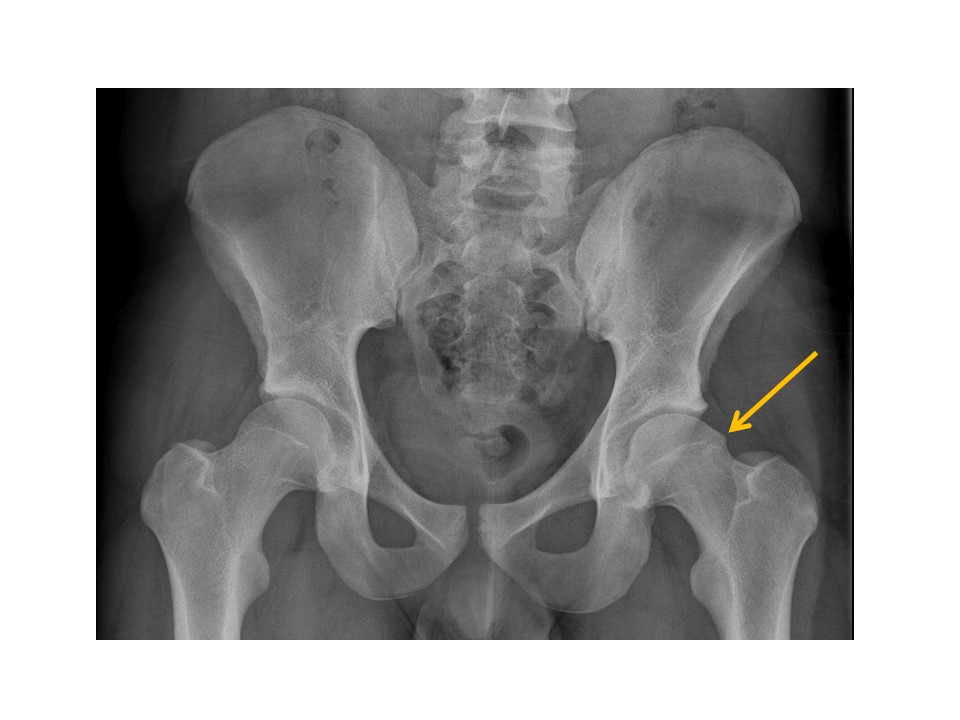

There are avulsion fractures at the ischial tuberosities. [Yes/No]

Ischial spine avulsion fractures are present. [Yes/No]

There are avulsion fractures of the greater or lesser trochanters.

[Yes/No]